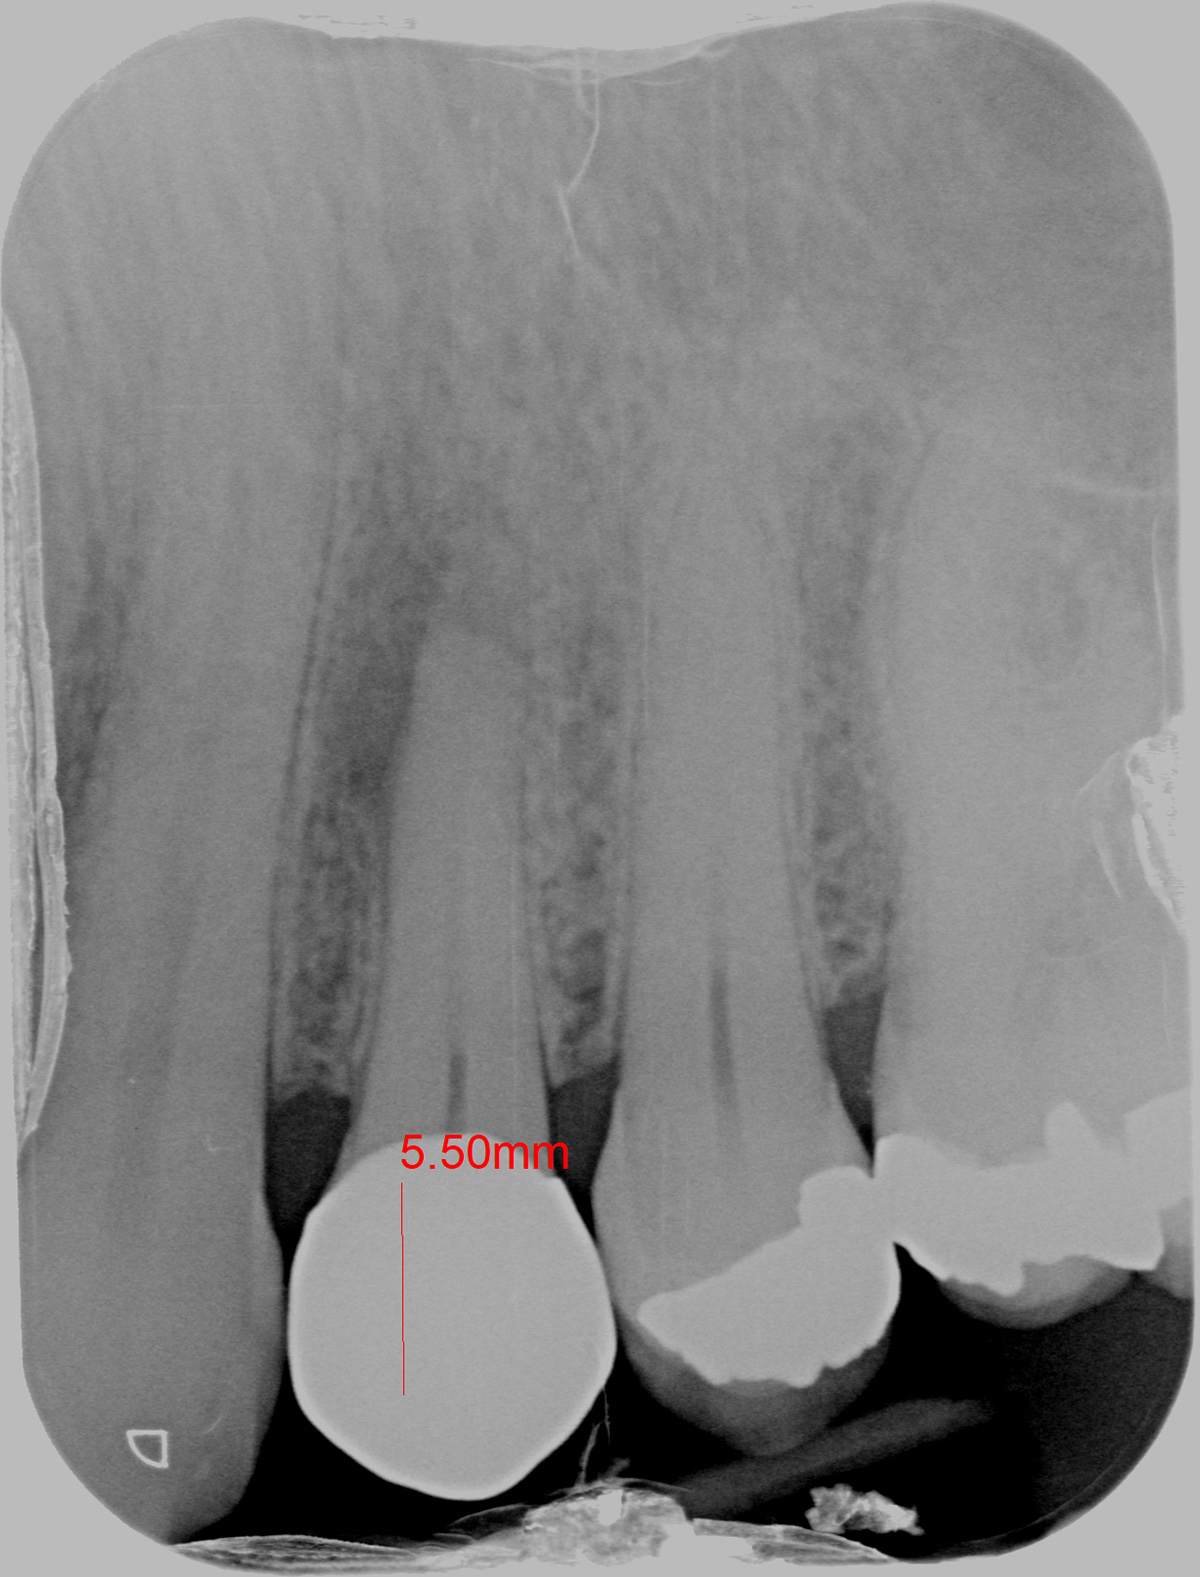

A CENTRAL INCISOR

INITIAL

WORKING LENGTH

FINAL

6 MONTHS FOLLOW-UP